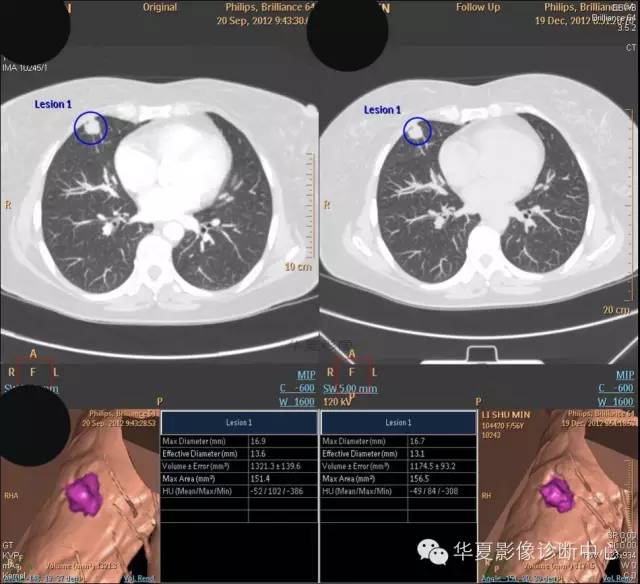

女,56岁,其父因肺癌去世,自觉胸部疼痛不适来诊要求拍胸片。

检查所见:

1.右肺上叶:肺组织1块,大小13×4×7cm。切面棕红色。2.右肺上叶肿物:灰白色组织一块,大小3×1×1.5cm。切面灰白色。3.右肺中叶结节:灰白色绿豆大组织1块。4.淋巴结:灰黑色绿豆大组织1块。

检查结论:

(右)肺中分化鳞状细胞癌。浸及胸膜。支气管残端切净。淋巴结未见癌转移(0/10)。